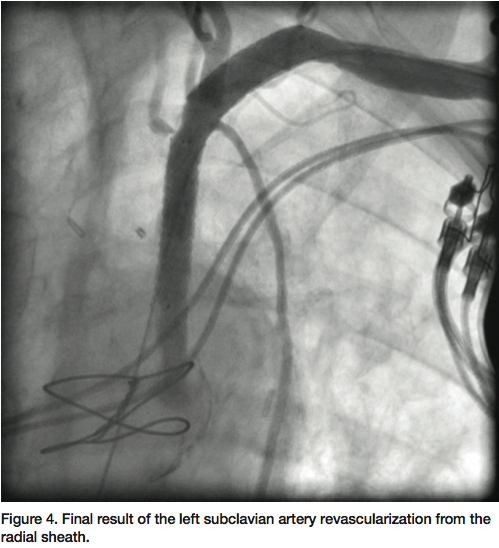

gram tip weight (Asahi Intecc) was used through a 6 Fr JR 4 diagnostic catheter to insert through the distal cap of CTO. Later, a Quick cross catheter (Spectranetics) was used to support the crossing of the CTO, and the wire was inserted into the ascending aorta. The JR 4 catheter and a short 6 Fr Glidesheath were exchanged over the 0.018” wire with a 45 cm, hydrophilic-coated Ansel sheath (Cook). Guided by dual injections from the aorta (femoral access) and the radial sheath parked in distal subclavian, a 6 x 37 mm and 6 x 17 mm balloon-

expandable stents were deployed into the subclavian. A 7 mm balloon was then used to post dilate both stents. TIMI-3 flow was re-established in the vertebral, IMA and in the LAD with an excellent final result (Figure 4). The patient had an uncomplicated hospital course and had remarkable improvement of his symptoms by the time of his clinical follow-up.